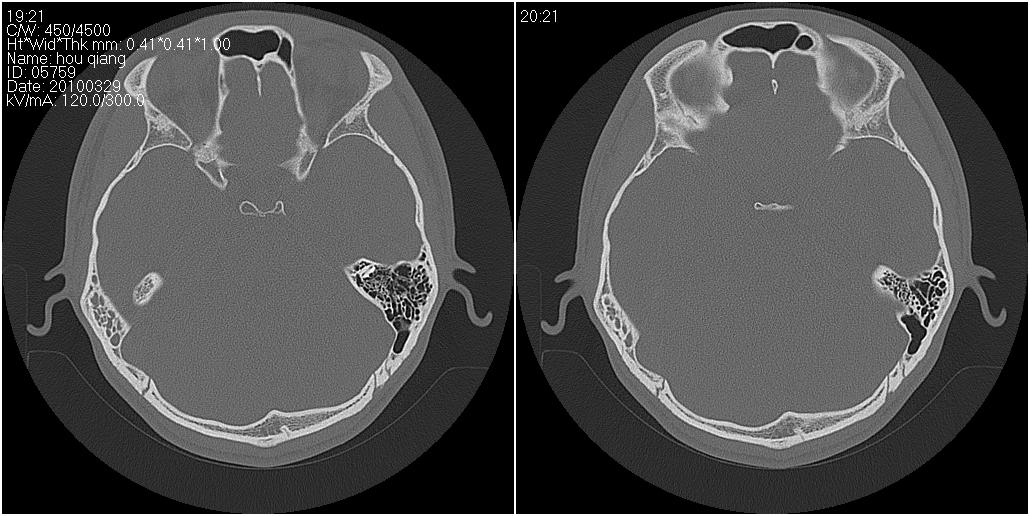

标题: CT25419:男性,18岁。右耳肿、痛5个多月。 [打印本页]

标题: CT25419:男性,18岁。右耳肿、痛5个多月。

右侧中耳乳突炎累及外耳道,鼻咽腺样体肥大。

1)右侧慢性中耳乳突炎并右侧中耳腔及外耳道肉芽肿或胆脂瘤形成。2)鼻咽腺样体肥大。